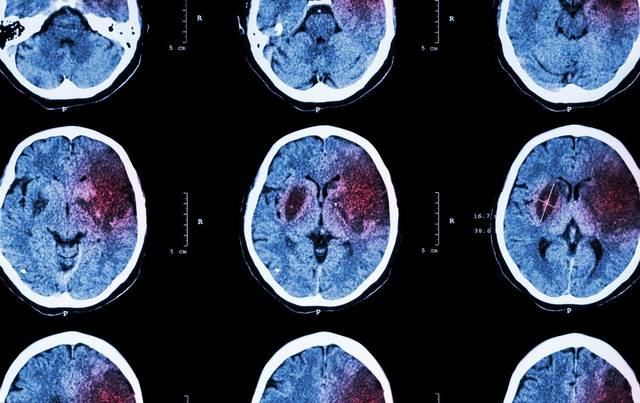

高血压起病隐匿,病程长达十几年至数十年,在起病初期,几乎没有感觉。但高血压对身体器官的损伤却是一直在持续,等到发现症状时再去治疗,往往来不及。高血压会影响心、脑、肾、眼底和血管等器官的功能,是心衰、脑卒中、尿毒症、心肌梗死等疾病最直接的病因,哪一个都是致命的疾病。所以医学上常说高血压是一个“沉默的杀手”。